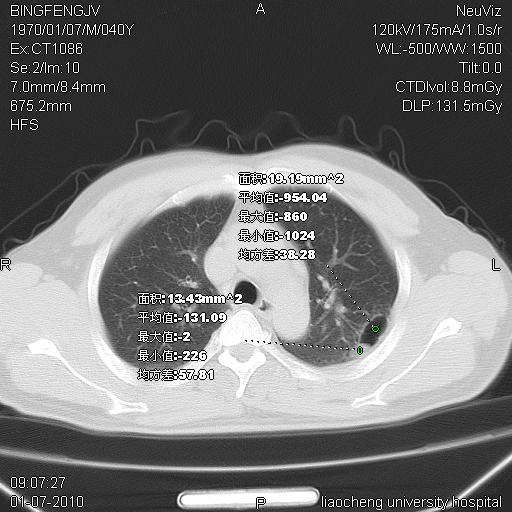

标题: CT23764B:男 40 肺部CT [打印本页]

标题: CT23764B:男 40 肺部CT

治疗2周后

考虑左肺上叶近胸膜下炎症并肺气囊形成。

炎症,大部吸收。